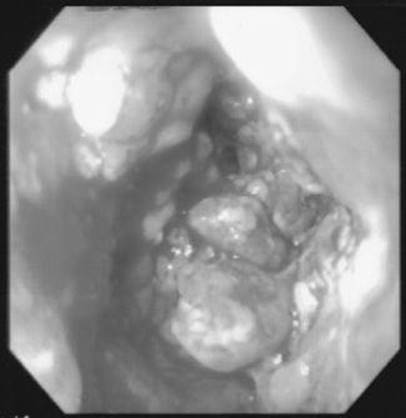

A 63-year-old “vasculopath” presents with massive GI bleeding about 6 weeks after another episode of bleeding during which an esophagogastroduodenoscopy (EGD) and colonoscopy were normal. An emergent CT scan is obtained. What is the diagnosis?

Figure 1-4

An aorto-enteric fistula. The so-called “herald bleeding episode,” in which significant bleeding that spontaneously ceases occurs, is characteristic of this condition. Although CT scan is more sensitive than endoscopy to diagnose this condition, the sensitivity of CT is still relatively low. This diagnosis, therefore, requires a high index of clinical suspicion. Endoscopy is often necessary to exclude a peptic process as a cause of the bleed but should be done in conjunction with surgery.